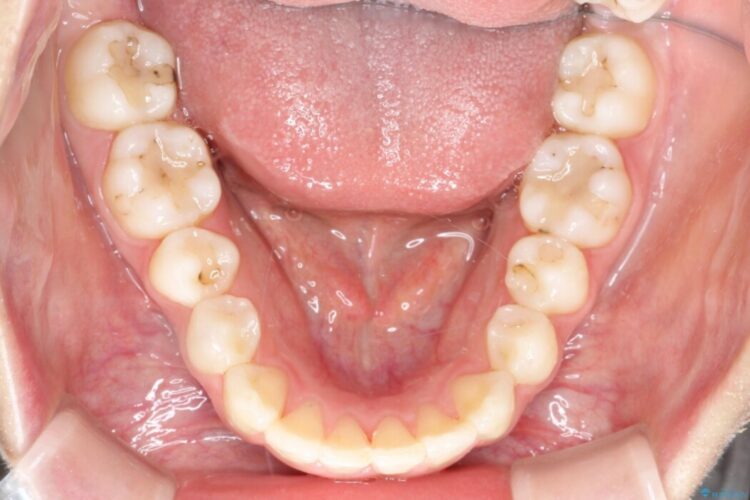

治療後について

マウスピース矯正は22時間以上の装着を推奨しております。

今回患者様にしっかりと装着していただけたため、きれいな歯列へと整えることができました。